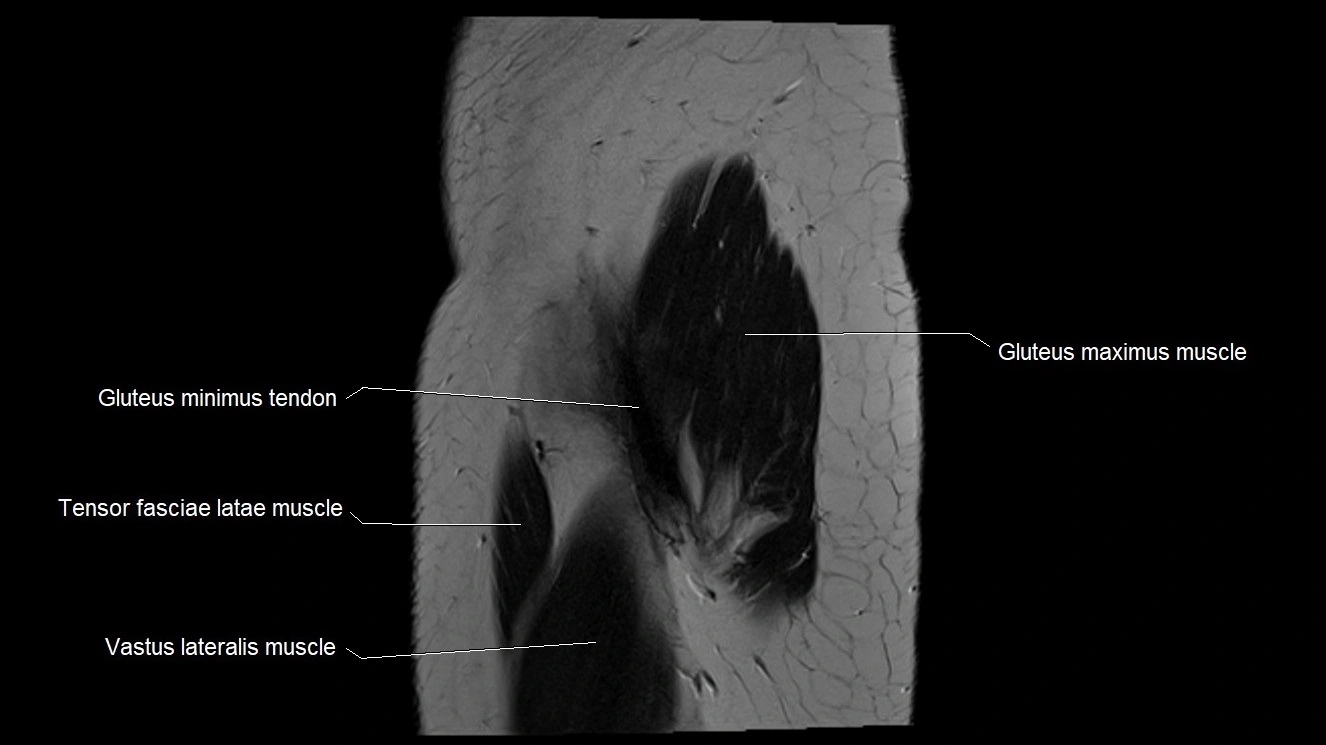

- Gluteus maximus muscle

- Gluteus minimus tendon

- Tensor fasciae latae muscle

- Vastus lateralis muscle